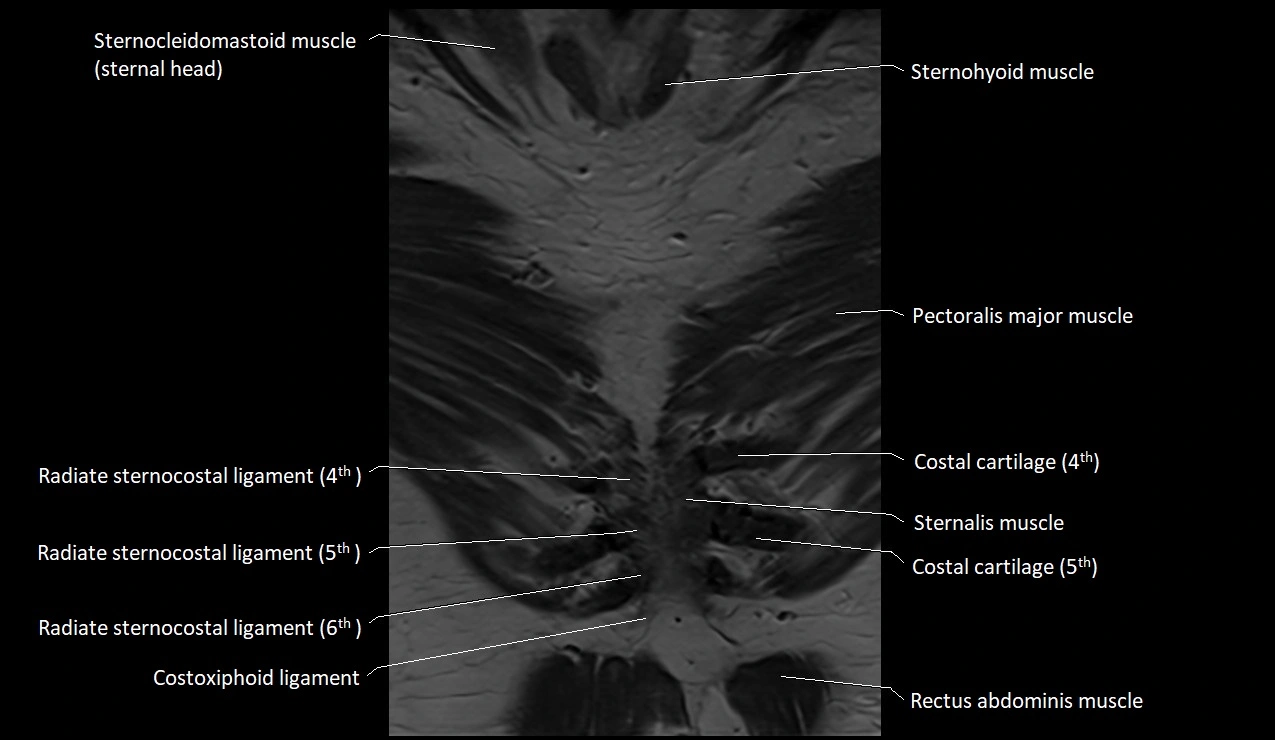

MRI images

image